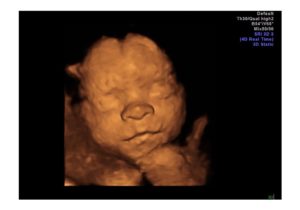

3Д УЗИ делается при беременности с целью детального просмотра частей тела, черт лица плода. При исследовании на экран ультразвукового устройства передается объемное голографическое изображение.

Трехмерное сканирование плода при беременности дает возможность в объемном виде оценить состояние ребенка. Картинка передается на экран аппарата в цветном режиме. Чаще метод используют на втором плановом скрининге, когда четко видны части тела плода.

Трехмерное изображение представляется в 3 измерениях — глубине, высоте и ширине. Беременная может увидеть ребенка на экране УЗИ-аппарата в цвете. При этом детально просматривается каждая часть лица и тела, мимика плода.

На смену обычному ультразвуковому 2Д-сканированию приходит 3Д и 4D УЗИ при беременности. Особенность последнего режима состоит в транслировании телодвижений плода в реальном времени.

Переданная на дисплей картинка поворачивается под любым углом. В результате 4D УЗИ плода врач безошибочно интерпретирует результат диагностики. Изображение при этом более четкое, чем при 3Д УЗИ.

У него неплохо выражены черты лица. Проводимое 3D-УЗИ в 25 недель позволит увидеть то, как будет выглядеть маленький человек, когда родится. Глаза еще закрыты, брови только начали развиваться, рот сформировался. Продолжает развиваться ушная раковина.